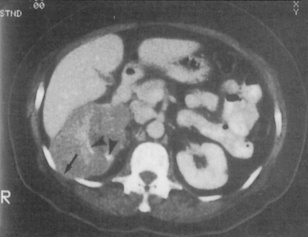

Computed tomography (CT) is a quick and non-invasive technique, which can be used with or without contrast. It is used to define renal and retroperitoneal masses and is ideal for locating and staging renal tumours (Fig. 8.20). It is also used to show polycystic kidney disease and has the advantage of also highlighting non-renal pathology. Modern techniques involving spiral CT can be used to visualize the anatomy of the renal arteries, renal vein and inferior vena cava, as well as retroperitoneal studies. Increasingly, CT without contrast is the investigation of choice to diagnose obstruction to the urinary tract or renal calculi (Fig. 8.21).

image

Fig. 8.20 CT scan highlighting a right renal cell carcinoma that extends through the intercostal space between ribs 11 and 12 (arrow) and medially along the renal vein. The high density (white) areas (arrows) indicate calcification.

(From Williams G, Mallick NP, 1994. Color atlas of renal diseases, 2nd edn. Mosby Year Book.)